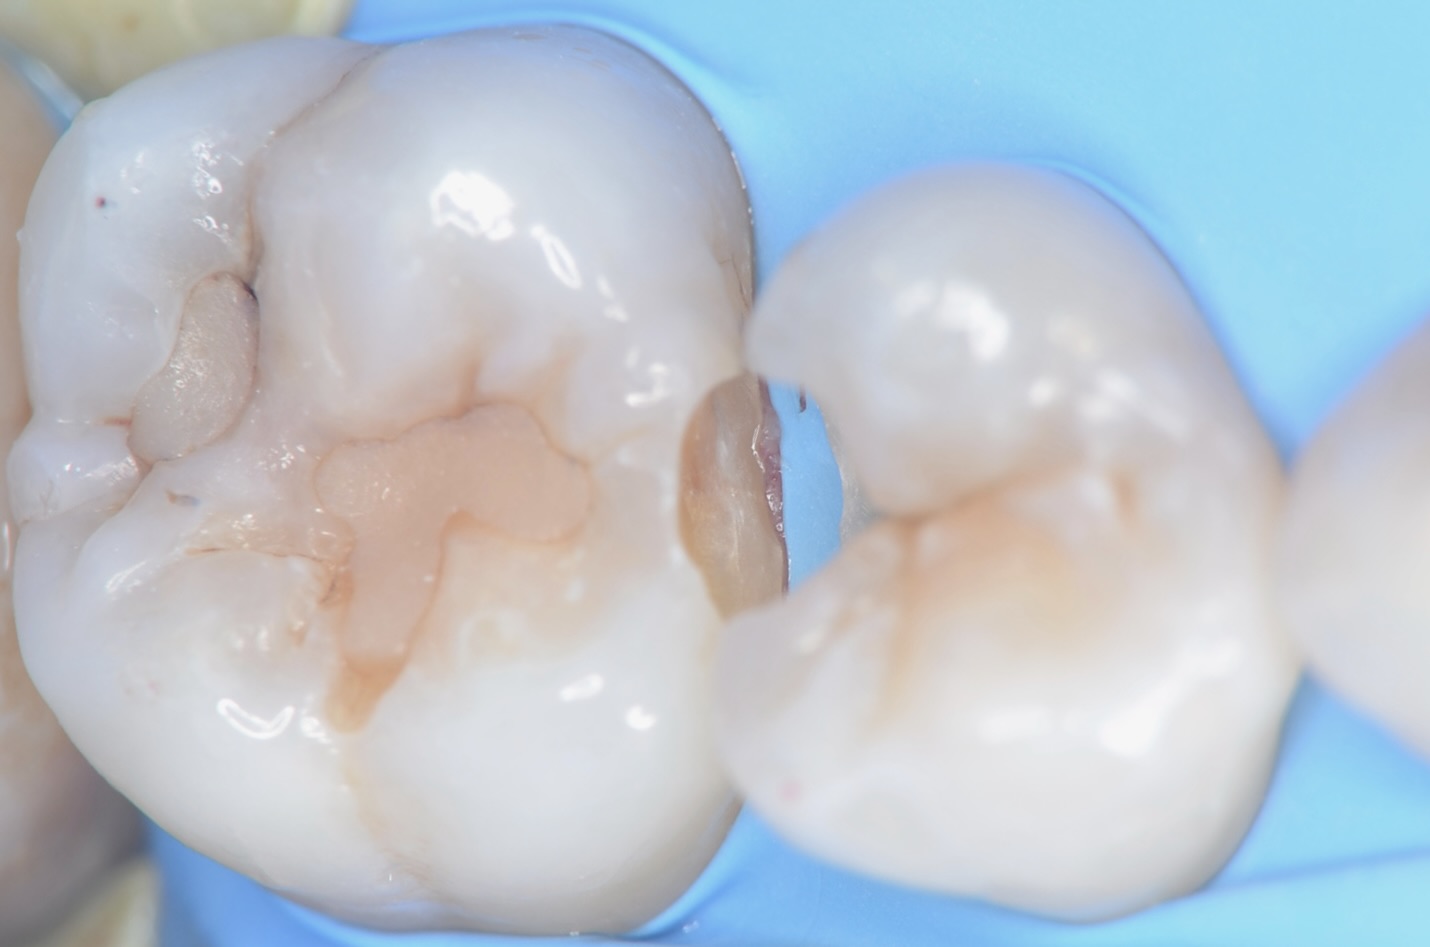

5番虫歯除去終了

青い齲蝕検知液で虫歯を染めて染まった部分を削ります。この工程を青く染まらなくなるまで歯にできるだけダメージがないように優しい力で丁寧に行います。この作業は時間がかかります。保険診療の短い時間で行うことは無理があります。 -

6番虫歯除去終了

-

知覚過敏抑制材の塗布

虫歯は神経すれすれでしたが、露髄はしなかったので知覚過敏抑制材を象牙質にすり込みました。ハイドロキシアパタイトで象牙細管を封鎖することにより知覚過敏を抑制します。大きな虫歯の治療後は違和感が出やすいので予防的にこの様な処置もしています。 -